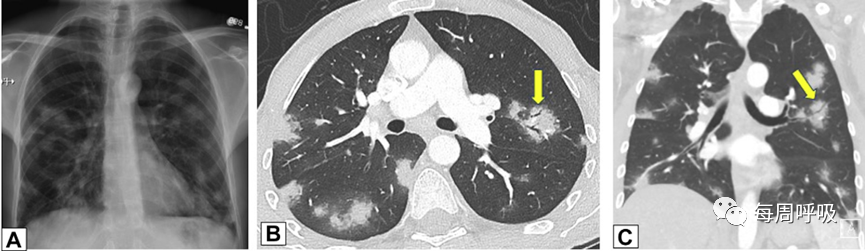

实变是OP病例中最常见的发现,发生在近75%的病例中,病变通常在双基底、支气管血管周围和/或外周(图2,3)。实变可以发生在肺的任何部位,边界清晰或模糊,呈游走性的特点(图4,5),可以呈局灶性,多发性和弥漫性,也可以表现为结节或肿块(图6)。实变常伴支气管充气征,可伴散在的磨玻璃样低密度或小实质结节。以主要的或完全的磨玻璃低密度为表现的较少见(图7)。磨玻璃低密度合并小叶间隔增厚可表现为铺路征(图8)。

图2 外周实变。2例患者CT轴位平扫图像。A,这张图片显示了一名女性右肺上叶周围实变,她曾因乳腺癌接受过放射治疗,并经活检证实为机化性肺炎(OP)。B,此图像显示左肺下叶和舌叶周围实变,活检证实为继发于淋巴瘤化疗的OP。

图3 支气管血管束分布 在活检证实的机化性肺炎患者中,通过中(A)和下(B)肺区的轴位增强CT扫描图像显示双侧多灶性支气管血管周围实变灶。

图4 OP游走性。A, 71岁男性,2011年7月因劳力性呼吸困难就诊,胸片显示右肺上叶实变。B, 2012年6月再次检查显示右肺上叶异常已消失,左肺出现广泛实变。C, 2013年6月,左肺病变消失,但右肺下叶出现新的实变。这些发现是典型的OP的游走性表现。

图5 – A-C,机化性肺炎的游走性CT表现。该患者与图4中的患者相同。

图6 多灶性、支气管血管周围肿块样实变。患者为70岁女性,确诊COVID-19 9个月后出现持续气促,CT轴位平扫图像显示支气管血管周围多灶性肿块样实变。在类固醇治疗后症状显著改善和实变消退,推测诊断为机化性肺炎。